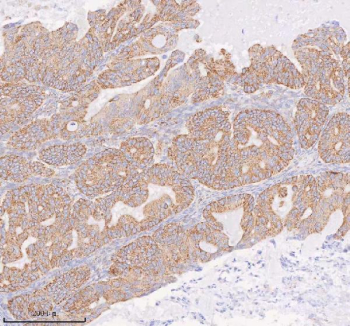

Immunohistochemical staining of COQ8B using anti-COQ8B antibody. COQ8B was detected in a paraffin-embedded section of human ovarian cancer tissue. Heat mediated antigen retrieval was performed in EDTA buffer (pH 8.0, epitope retrieval solution). The tissue section was blocked with 10% goat serum. The tissue section was then incubated with 2 ug/ml rabbit anti-COQ8B antibody overnight at 4oC. Peroxidase Conjugated Goat Anti-rabbit IgG was used as secondary antibody and incubated for 30 minutes at 37oC. The tissue section was developed using an HRP secondary and DAB substrate.